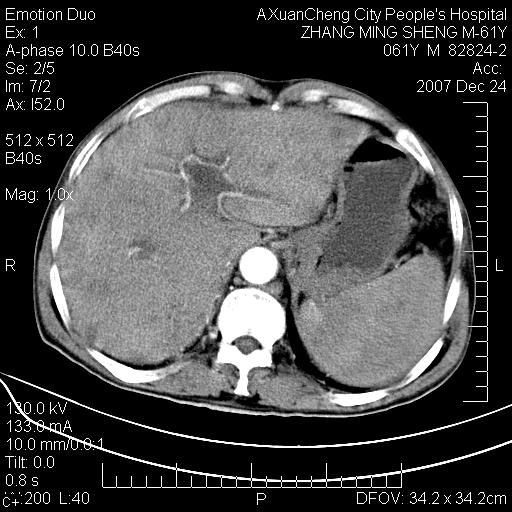

标题: CT11031:M61Y,胰腺占位

大家侃侃门静脉和胆管系统怎么回事,肝内转移?

胰腺癌肝转移

肝硬化,门脉高压,脾肿大;弥漫性肝癌,肝内、门脉、腹膜后淋巴结转移,肝内外胆管扩张,胰头区占位,建议mr检查

胰腺癌伴肝内转移;门脉、肠系膜上v癌栓形成。